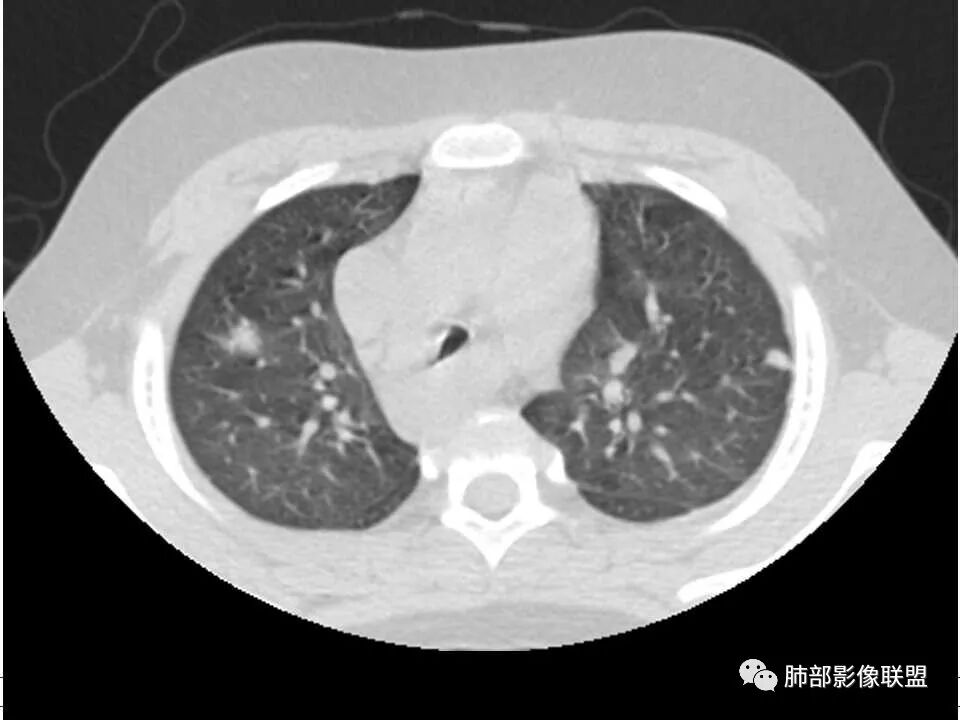

有脓毒性肺栓塞了,有空洞,有结节,有血管滋养征,考虑血源性金葡菌感染

患者儿童,因右下肢疼痛伴肿胀14天就诊。病程中有发热及伴随症状。膝关节MRI提示右侧膝关节及右髌骨髁异常信号影,右膝髌上囊及关节腔内少量积液。胸部CT:双肺胸膜下多发结节影,部分结节空洞形成,且结节周围可见血管集束征。综合考虑血源性脓毒性肺栓塞、坏死性肺炎。右侧骨髓炎、血播性金葡菌肺炎,鉴别其他特殊感染及血管炎。

胸部ct:双肺多发空洞,结节,外带下叶为主,空洞内外光滑,有血管滋养征,综合病史及影像考虑脓毒性肺栓塞,结合病史,金葡可能性大。

男,8岁,两肺多发随机分布结节空洞影,壁光整,考虑血道来源,结合右侧膝关节有骨髓水肿信号,临床感染指标明显增高,考虑骨髓炎并血道播散,金葡菌感染?LCH小孩骨头症状相对较轻,放在代排吧。

小儿,急性起病,下肢疼痛,mr提示骨髓水肿,临床化验炎性指标高,考虑金葡菌骨髓炎,双肺多发结节,以血管支气管束及胸膜下分布为主,部分结节近端与血管相连,部分结节可见空腔,内壁光整,部分囊腔有张力,考虑骨髓炎并肺内血播感染,金葡?

2.双肺多发片影,随机分布,多空洞或囊腔,胸膜下多楔形影,气道未见受累等等符合脓毒血症影像学表现,尤其是金葡。

2、脓肿:实变区内脓肿,最常见吸入性金葡菌引起的多,下叶多见,在实变区中央,外壁不清,内壁光滑,可见气液平面;血源性脓肿,多发,结节状,大小无差异,边清,光滑,壁薄;

1. 多发胸膜下外周结节、< 3 cm 的楔形影和滋养血管征 CT 表现;

4.经恰当的抗生素治疗,肺部浸润影吸收。滋养血管征为一支血管影连接肺部周边病灶,在 2/3 以上患者出现,可作为高度提示 SPE 的征象。